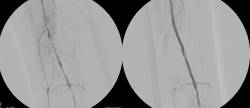

Mediante minuciosa anamnesis, exploración y eco-doppler en la propia consulta (consultas de alta resolución) se planifica el tipo de tratamiento más adecuado para cada paciente, desde el tratamiento médico hasta la cirugía abierta convencional, pasando por las modernas técnicas mínimamente invasivas como la esclerosis, el láser endovenoso o la combinación de ellos en el caso de las varices o las endoprótesis aórticas en el caso de los aneurismas o las técnicas endovasculares en las extremidades.

La patología arterial obstructiva y aneurismática se maneja de manera integral por nuestro equipo y se ofrecen los tratamientos médicos, quirúrgicos o endovasculares de última generación, con especial interés en las angioplastias con o sin stent, las endoprótesis aórticas, los accesos vasculares para hemodiálisis y el tratamiento endovascular de la hipertensión refractaria.

Una vez diagnosticados los aneurismas de aorta suelen tener solución. Un simple eco doppler abdominal sirve de cribado y en caso afirmativo se completa el estudio con otras pruebas de imagen. Después, en aquellos casos en que esté indicado, somos capaces de tratar la mayoría de los casos con modernas técnicas endovasculares mínimamente invasivas. Esto supone un gran avance médico y tecnológico, ya que se puede ofrecer un tratamiento efectivo a muchos pacientes que antes no podían tratarse por criterios anatómicos o de riesgo quirúrgico con resultados muy satisfactorios.

Mediante una historia clínica exhaustiva y una exploración física dirigida, es posible diagnosticar la claudicación intermitente en la mayoría de los casos, pudiendo apoyarse en pruebas diagnósticas poco agresivas, como el Eco-Doppler y el Doppler continuo, cuando se considera necesario.